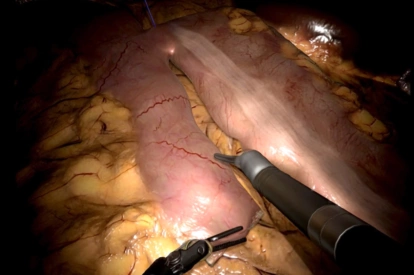

- Highly realistic graphics of human anatomy and simulation of tissue response to instruments

- Tutorials: videos of experts performing tasks and procedures on the simulator along with videos of real procedures